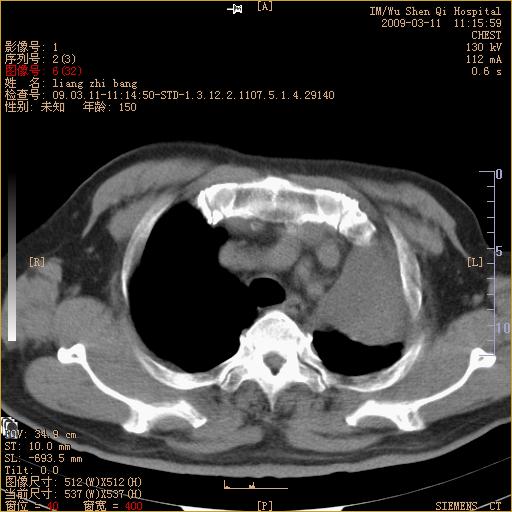

标题: CT18604:男,60岁,咳嗽一月余 [打印本页]

标题: CT18604:男,60岁,咳嗽一月余

1、左肺上叶中央型肺癌并上叶阻塞性肺不张。

2、左侧胸腔少量积液,右侧胸膜轻度增厚。